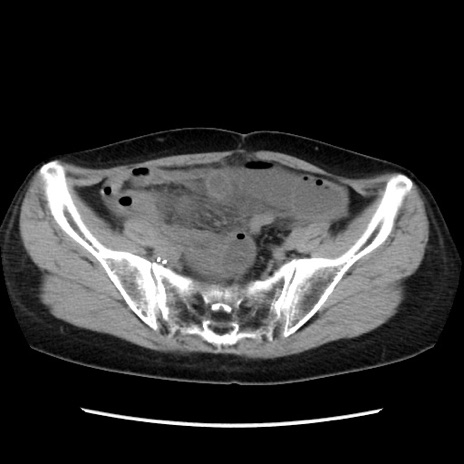

症例32(横断像)

【症例】40歳代 女性

【主訴】上腹部痛、嘔気・嘔吐

【現病歴】約9時間前頃から急に上腹部痛、嘔気、嘔吐が出現。改善しないため救急要請。

【既往歴】子宮頚癌(広汎子宮全摘術、放射線療法)、腸閉塞

【身体所見】腹部:平坦、軟、腸雑音亢進、上腹部を中心に腹部全体に圧痛あり。

【データ】WBC 8400、CRP 0.03